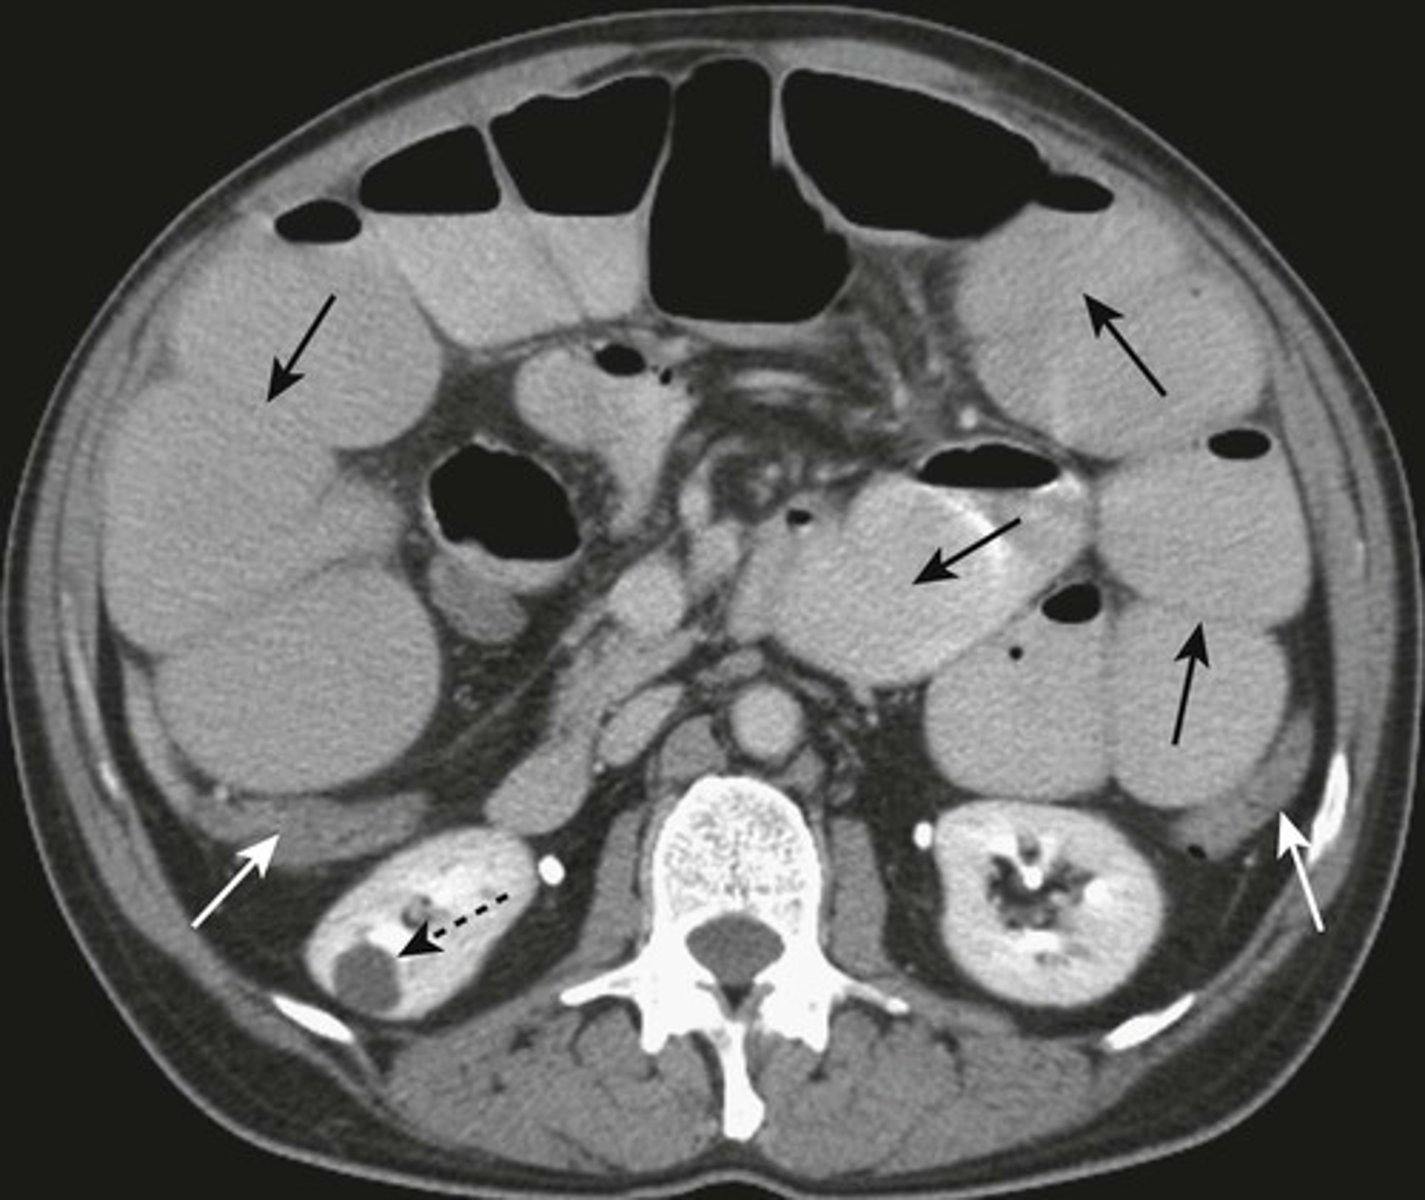

Medullary nephrocalcinosis.

WHITE ARROWS: cloudlike calcifications seen bilaterally.

suggests that these calcifications have formed within a solid organ or tumor.

The calcifications conform to the distribution of the renal collecting systems.

This is medullary nephrocalcinosis, a condition not synonymous with renal calculi because nephrocalcinosis signifies a metabolic derangement. This patient had primary hyperparathyroidism.